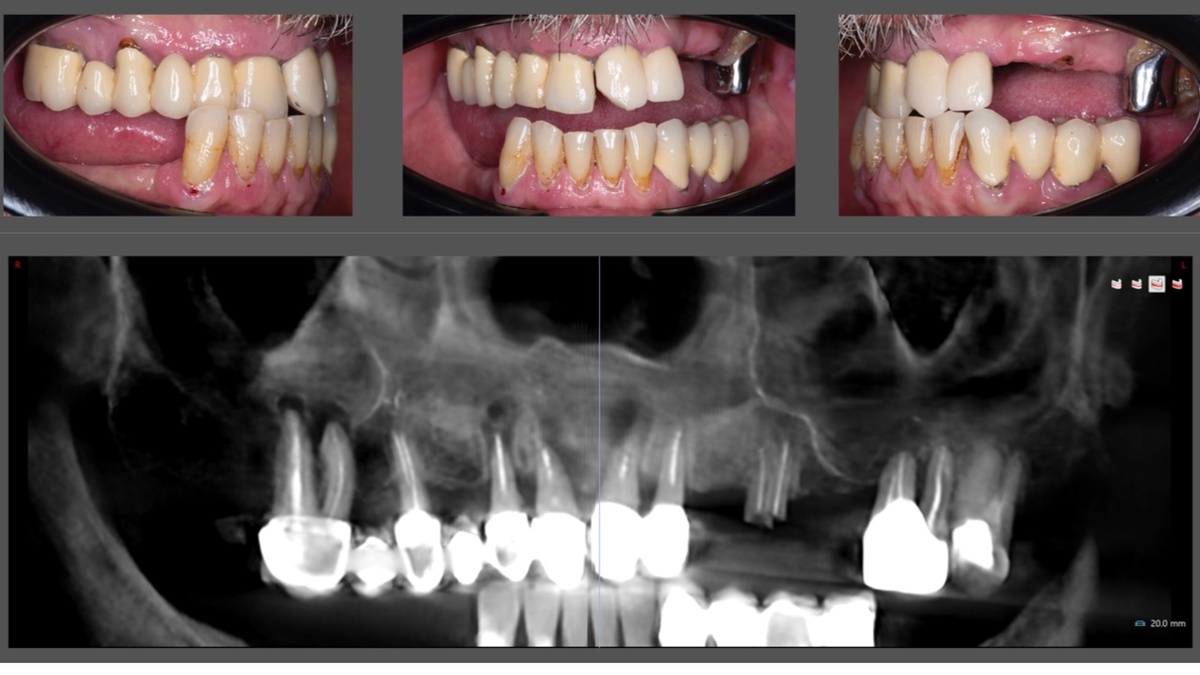

На момент обращения у пациента на верхней и нижней челюстях –несостоятельные конструкции, рецессии десны, корень 2.5.

После изучения данных объективного осмотра и КЛКТ составлен план реабилитации:

1. Удаление зубов верхней челюсти с имплантацией All-on-4 (Nobel Biocare) и немедленной нагрузкой временным протезом

2. Через 3 месяца удаление зуба 3.5 с имплантацией 3.4–3.6 и 4.4–4.6 по шаблону

3. Через 3 месяца после имплантации на нижней челюсти изготовление временных коронок на имплантаты 3.4–3.6 и 4.4–4.6

4. Через 8 месяцев после операции на верхней челюсти окончательное протезирование верхней и нижней челюстей.

Через 8 месяцев пациент пришел в клинику с фиксированными временными конструкциями на верхней и нижней челюстях. На верхней челюсти – условно-съемный протез, изготовленный в день операции, на нижней челюсти - временные коронки на имплантатах в позициях 3.4–3.6, 4.4–4.6 зубов.